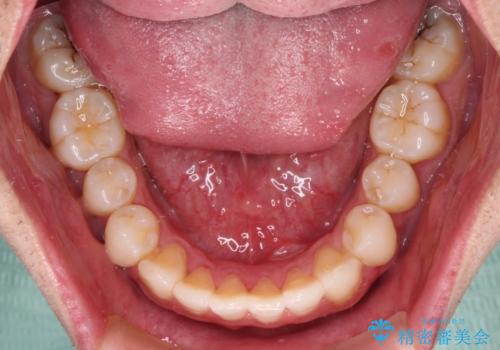

- 全体的なデコボコと、前歯の前に出ている感じを気にして来院された患者様です。

患者様と相談の上、非抜歯にてインビザラインを用いて矯正治療を行うこととし、IPR(歯と歯の間)並びに歯列全体の後方移動により口元の突出感の改善することとしました。